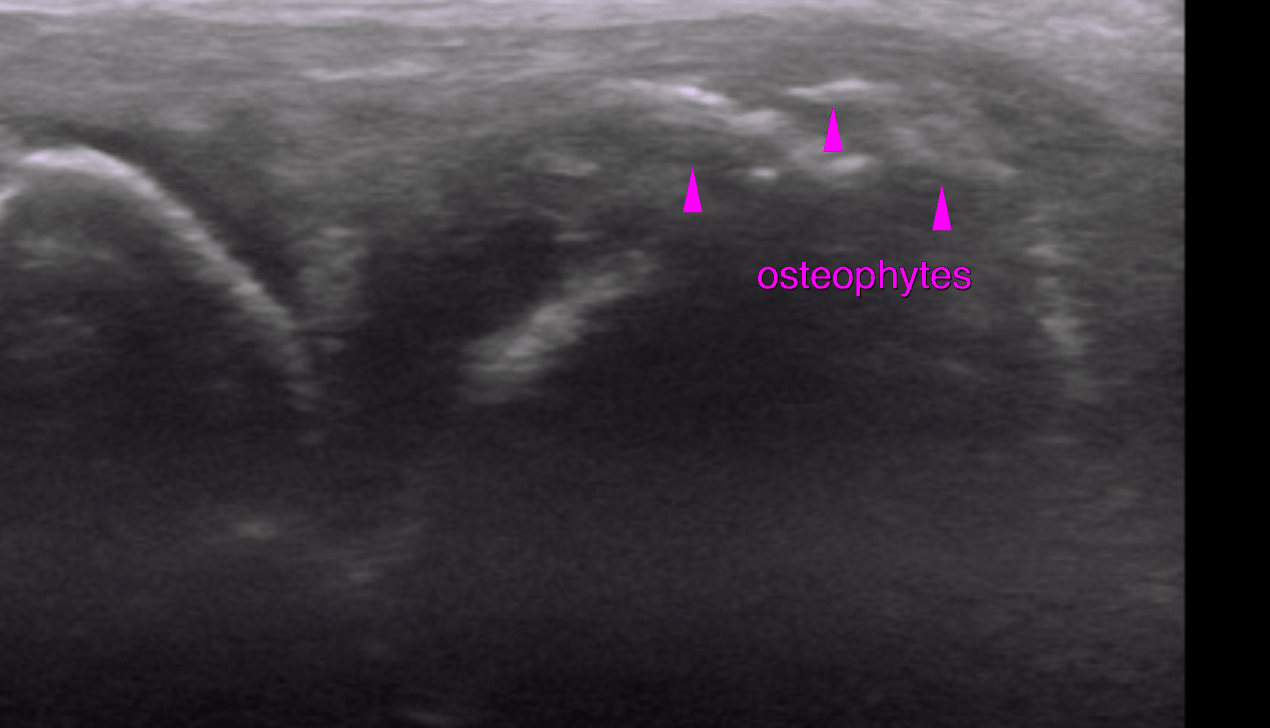

This 6 year old MN Belgian Shepherd dog has a history of intermittent lameness of over 1 year duration. Worsens with exercise. Decreased muscle mass right hind. Positive cranial drawer sign and CTT, moderate medial buttress sign.

Evaluate right stifle prior to TTA stabilization